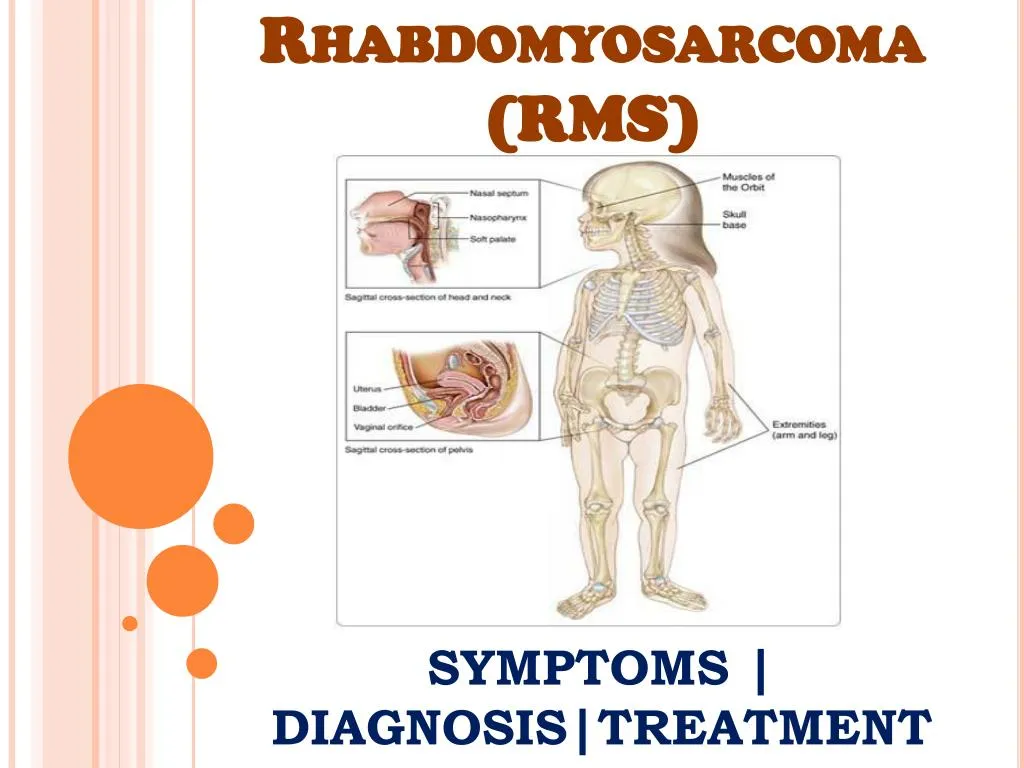

PPT - Rhabdomyosarcoma (RMS): Information On Symptoms, Diagnosis And

www.slideserve.com

www.slideserve.com

rhabdomyosarcoma rms treatment ppt diagnosis symptoms information powerpoint presentation